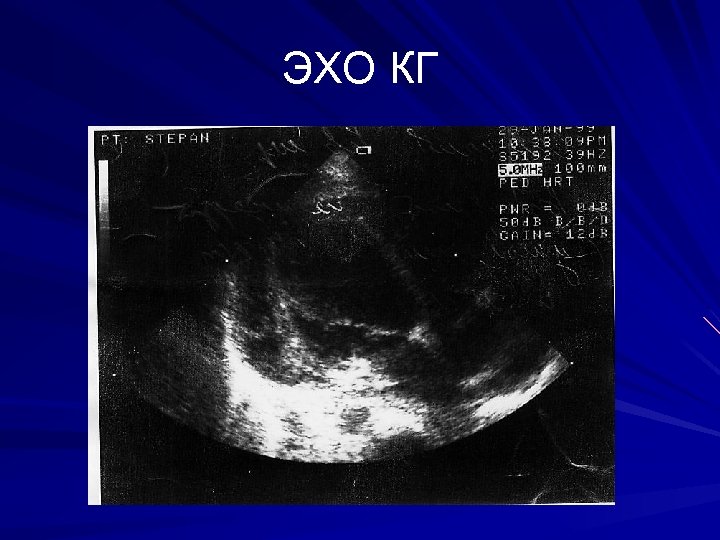

ЭХО КГ

ЭХО КГ